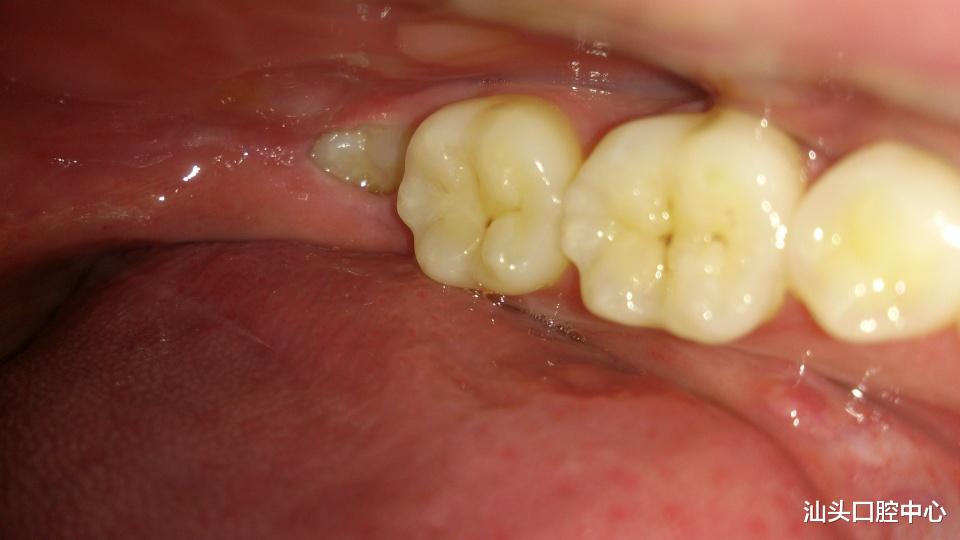

而萌出不正的智齿往往伴随着炎症 , 或者影响邻牙和对牙 , 让我们痛不欲生的同时 , 其他牙齿也受到损害 , 所以医生在检查了我们的口腔后 , 对于萌出不正会影响到其它牙齿的智齿 , 都会建议拔掉 。

汕头口腔医疗中心 , 如果智齿出现发炎肿痛的现象 , 一般是不建议拔掉的 , 因为局部浸润麻醉或神经阻滞麻醉效果不是特别好 , 在拔除智齿的过程中很容易造成局部感染的扩散 。 而且这样不仅会出血多、加重炎症 , 也会造成拔牙后愈合不好 , 可能会出现长期不愈合的干槽症的情况 。 而且拔牙后疼痛也会加重 , 无疑增加了的拔牙的痛苦 。 所以建议智齿发炎 , 先到医院冲洗上药消炎 , 等到炎症消除后再拔牙也不迟 。